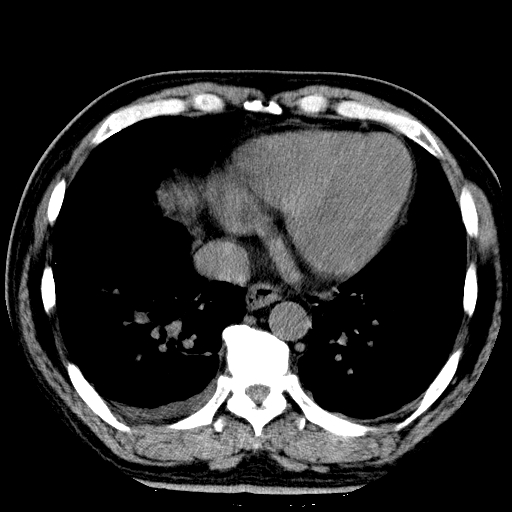

标题: CT21804:男,65岁,咳嗽、咳痰、发热5天。 [打印本页]

男,65岁,咳嗽、咳痰、发热5天。